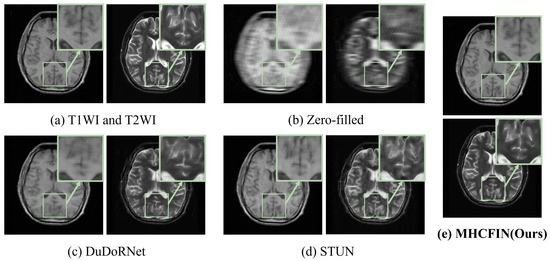

5.2. Qualitative Results